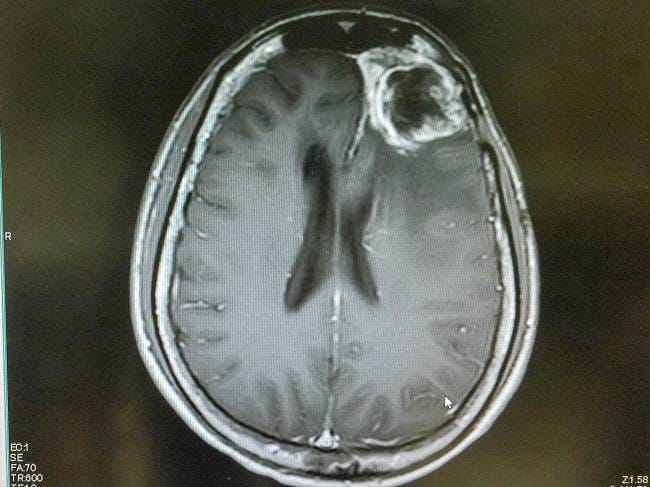

- MRI atau CT scan kepala untuk melihat lokasi dan ukuran glioblastoma